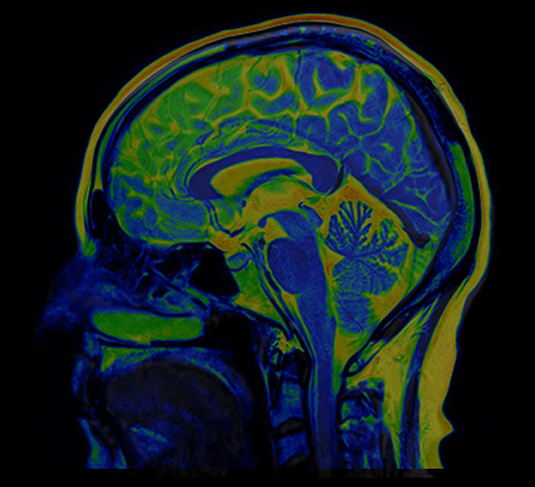

MRI brain scan

To investigate the neurobiological mechanisms of hallucinations and delusions within the framework of the hierarchical model, the researchers used functional magnetic resonance imaging to measure intrinsic neural timescales throughout the brain. These neural timescales reflect how long information is integrated in a given brain region. Most importantly, these neural timescales are organized hierarchically, making it a fitting measure to test the hierarchical model of psychosis.